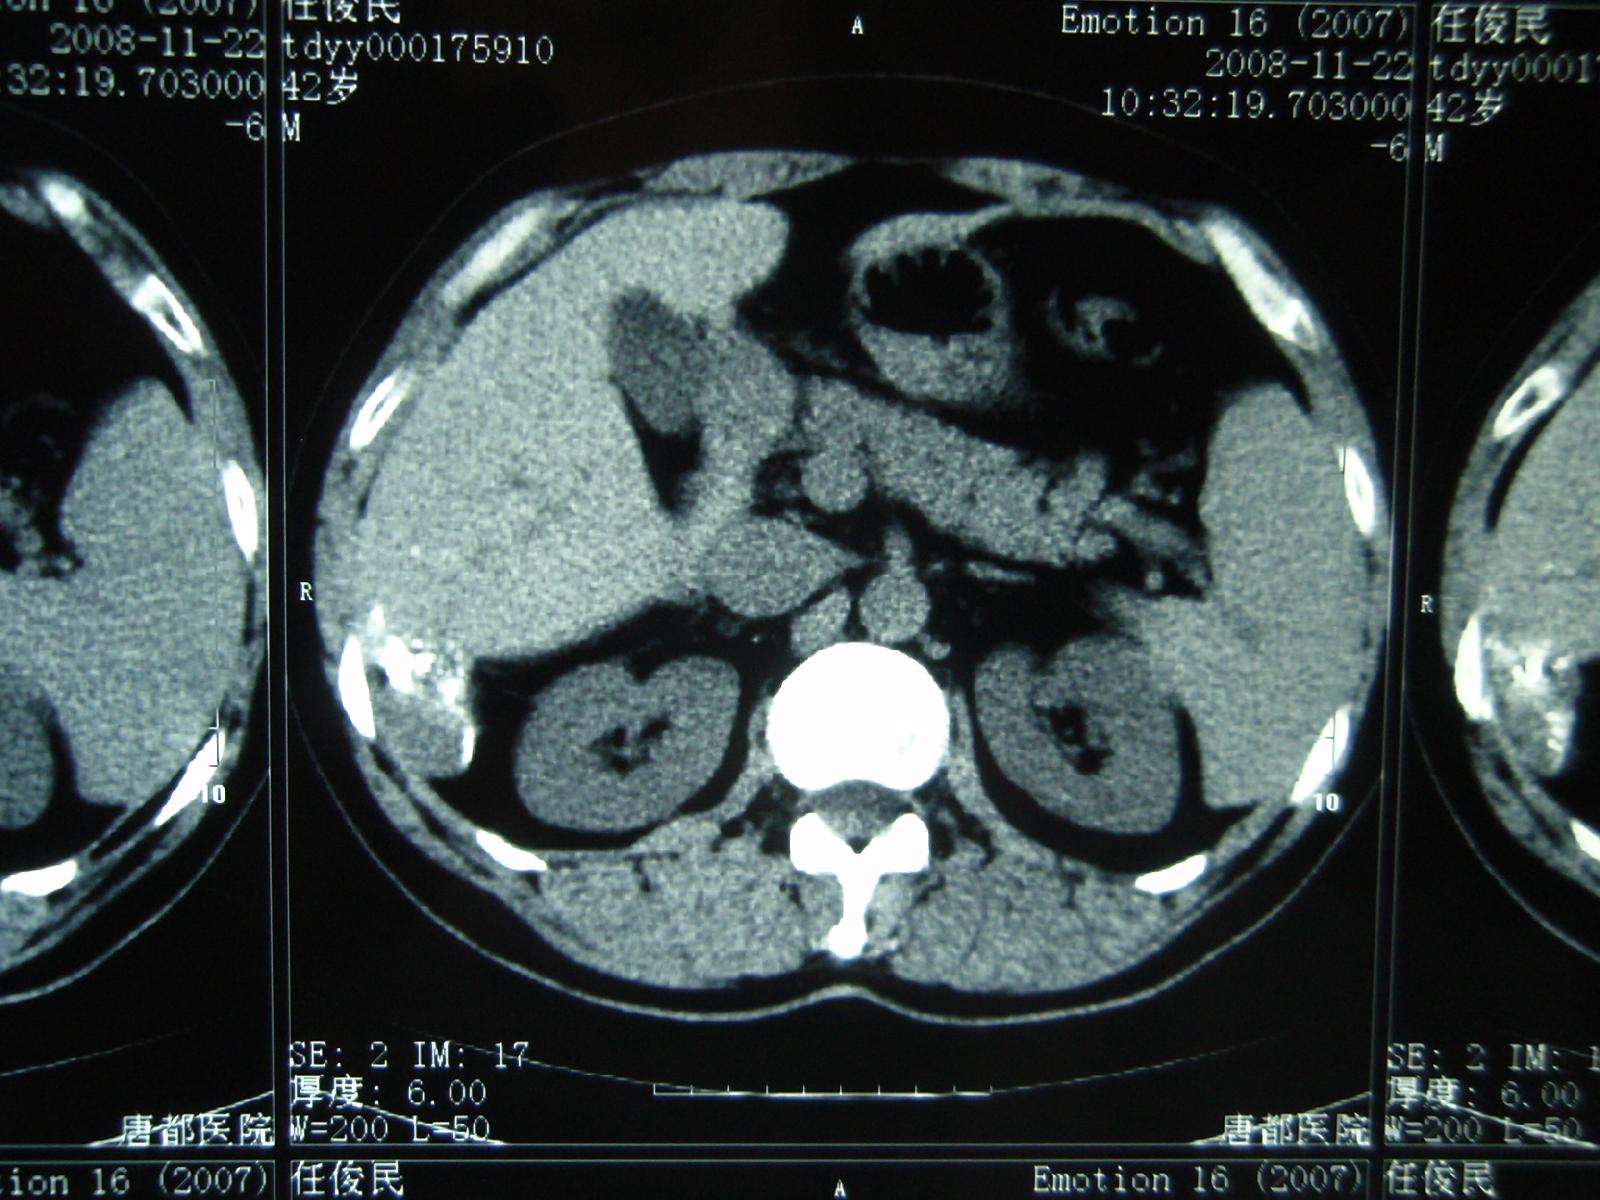

2008年11月22日,栓塞后8个月复查CT显示病灶进一步缩小,仅留一些碘化油沉积,相当于原来的几分之一,病灶完全治愈!